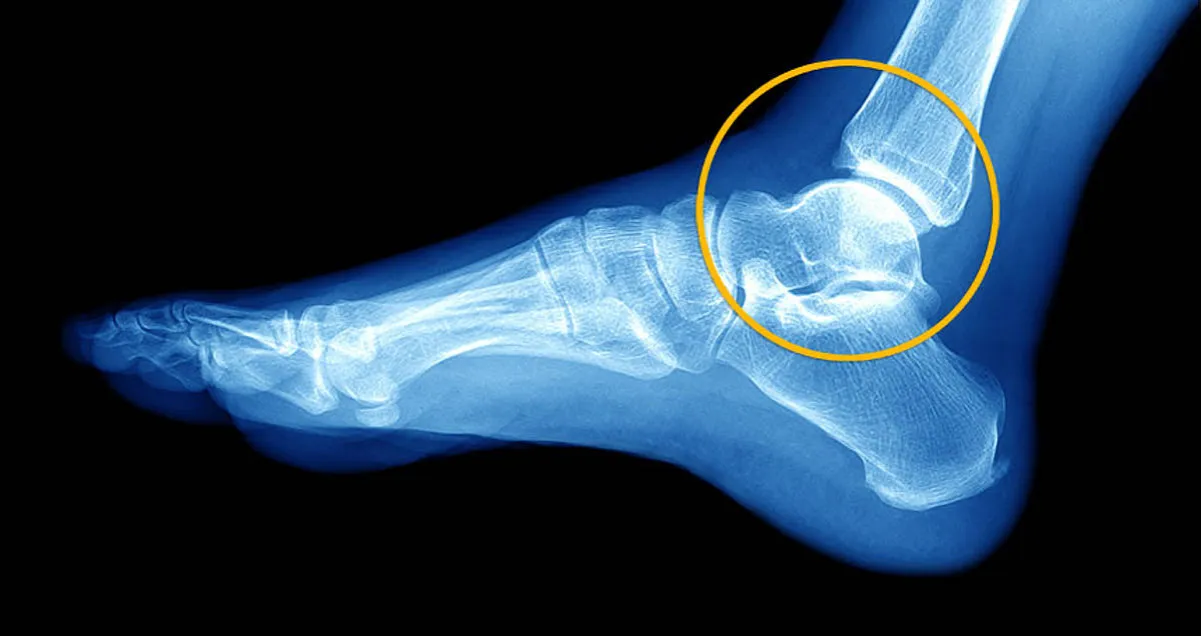

- Diagnostyka opiera się na badaniu fizykalnym i badaniach obrazowych (RTG, USG), które precyzyjnie określają rodzaj i stopień urazu.

Proces diagnostyczny zawsze rozpoczyna się od dokładnego badania fizykalnego przez lekarza, który oceni ból, obrzęk, deformację, zakres ruchu oraz stabilność stawu. Następnie kluczowe są badania obrazowe. Rentgen (RTG) jest niezbędny przy podejrzeniu zwichnięcia, aby ocenić ułożenie kości i wykluczyć ewentualne złamania towarzyszące. USG (ultrasonografia) jest często wykorzystywane do oceny tkanek miękkich więzadeł i torebki stawowej, co jest szczególnie pomocne przy skręceniach. W bardziej złożonych przypadkach, gdy potrzebna jest bardzo szczegółowa ocena struktur stawu, lekarz może zlecić Rezonans Magnetyczny (MRI).